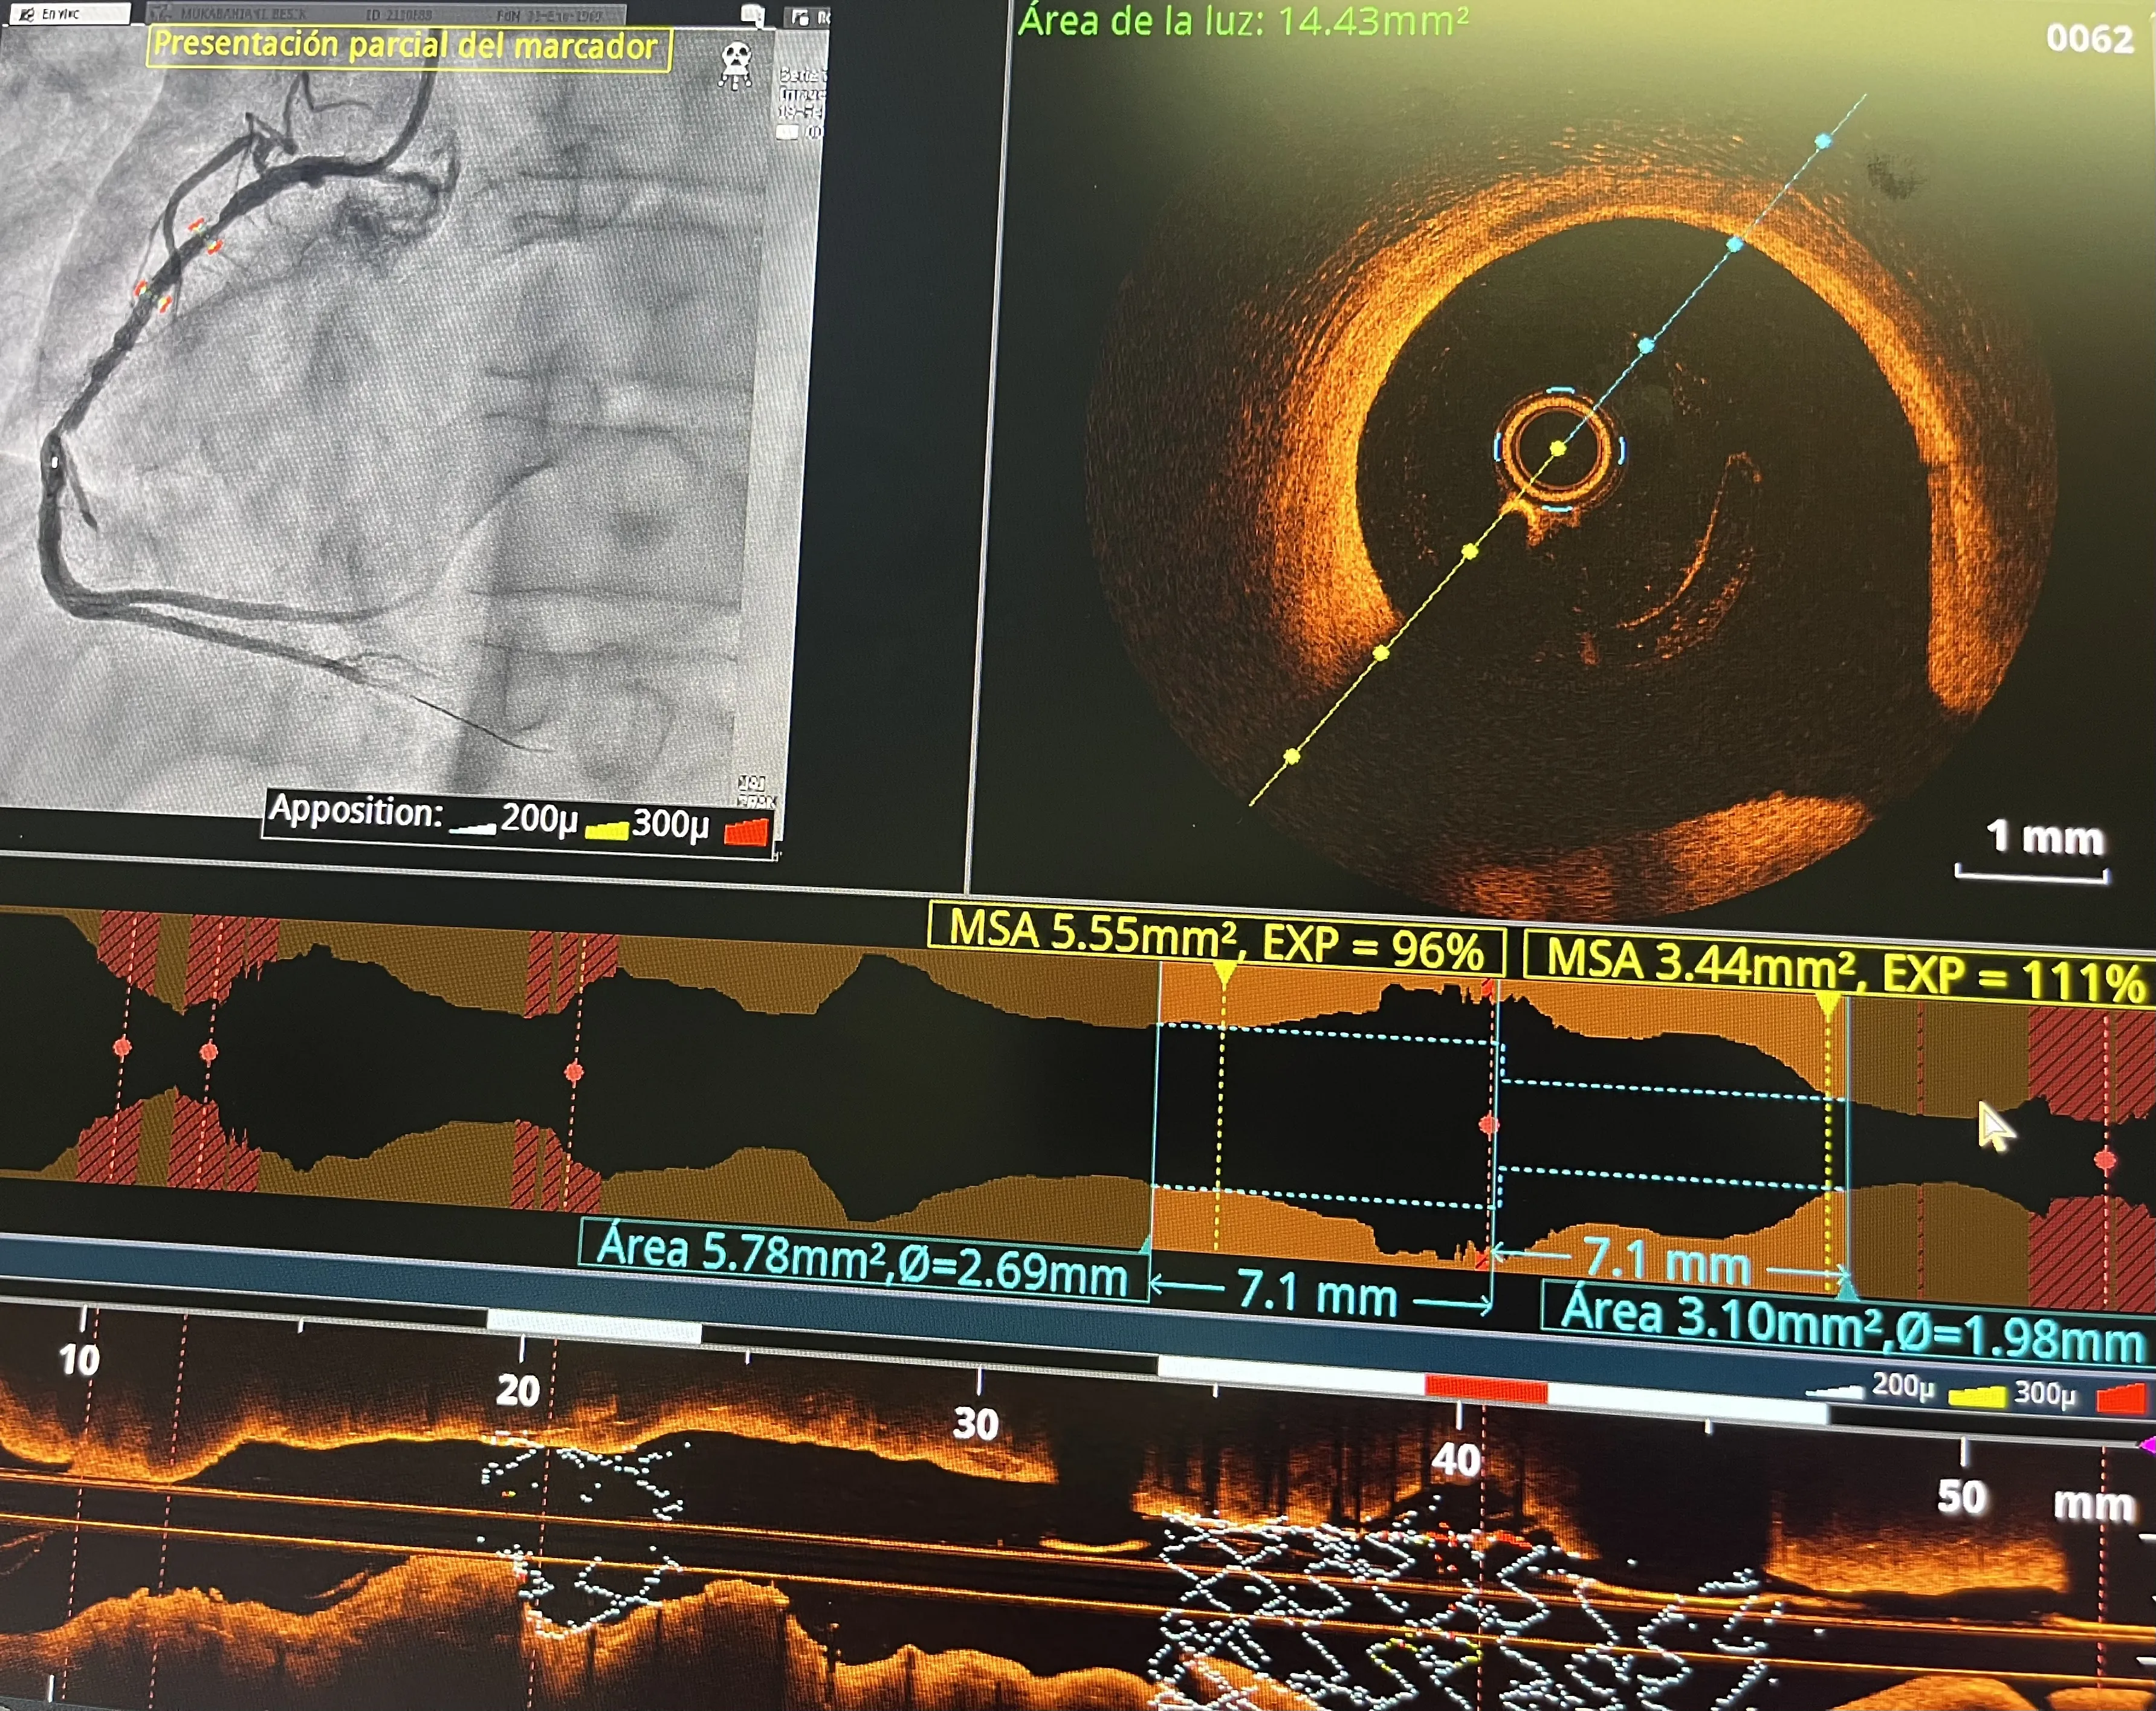

Uso de OCT en hemodinámica: evaluación de la reestenosis del stent

La técnica de OCT (tomografía de coherencia óptica) fue utilizada para evaluar la reestenosis del stent en este caso. Esta técnica ofrece imágenes de alta calidad dentro de las arterias, lo que facilita una evaluación precisa de la reestenosis y guía el tratamiento adecuado.

Ventajas de la técnica de OCT en la reestenosis

La OCT proporciona imágenes detalladas y de alta resolución, lo que permite una evaluación precisa de la reestenosis. Esta técnica es especialmente útil en casos complejos, ya que ayuda a identificar la extensión y la naturaleza de la obstrucción, facilitando así un tratamiento más efectivo.

Integración de OCT hemodinámica en la práctica diaria